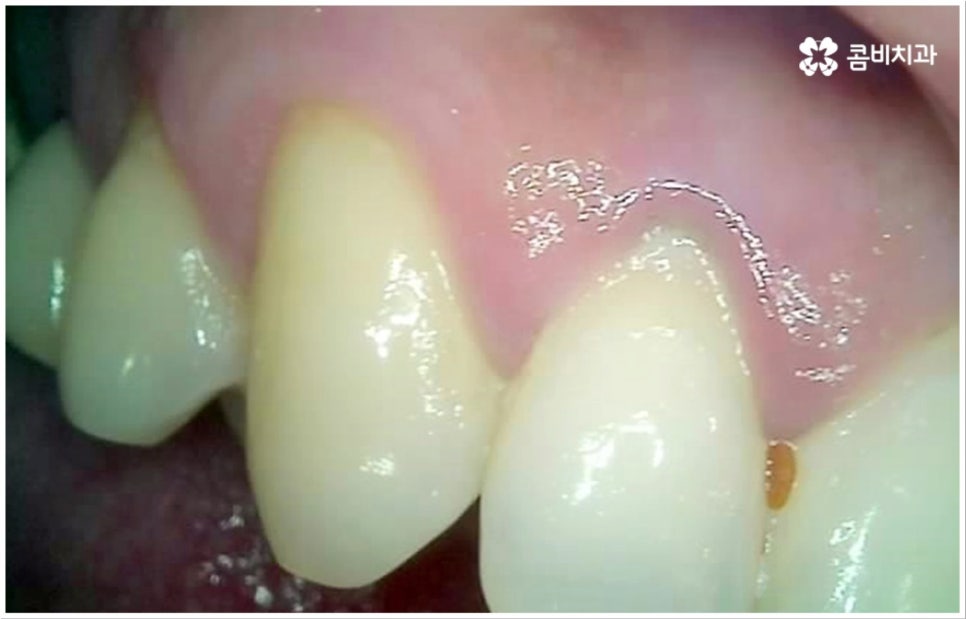

많은 분들이 살면서 한 번쯤 앓아봤을 충치는 이와 같은 교합면에만 발생하는 것이 아니라 치아와 치아 사이 인접면에 발생할 수도 있는데요. 인접면 충치는 치아끼리 맞닿은 좁은 틈새에 음식물 찌꺼기가 잘 끼고 또한 이것이 양치질을 통해서도 쉽게 빠지지 않아 관리가 어렵기 때문에 생기는 경우가 많은데, 교합면 충치에 비해 발견과 치료가 어려운 편이라고 할 수 있어요.

물론 앞니 등 노출이 되는 부위의 인접면 충치는 비교적 쉽게 알아차릴 수 있고 치료를 위한 접근 역시 용이한 편이나 어금니 인접면 충치 같은 경우 바로 드러나는 부위가 아니므로 육안으로 식별이 잘 되지 않고 엑스레이를 찍어도 초기에는 확인이 어려워 어느 정도 병증이 진행된 후 발견하게 되는 경우가 종종 있는데요. 치아의 인접면은 교합면에 비해 상대적으로 법랑질이 얇기 때문에 상아질 안 쪽 치수 신경까지 세균이 침투하는 속도가 빨라서 자칫 치료 시기를 놓치면 충치 통증 이 많이 심해지고 신경 치료까지 진행해야 하는 상황까지 발생할 수 있으니 조심하실 필요가 있습니다.